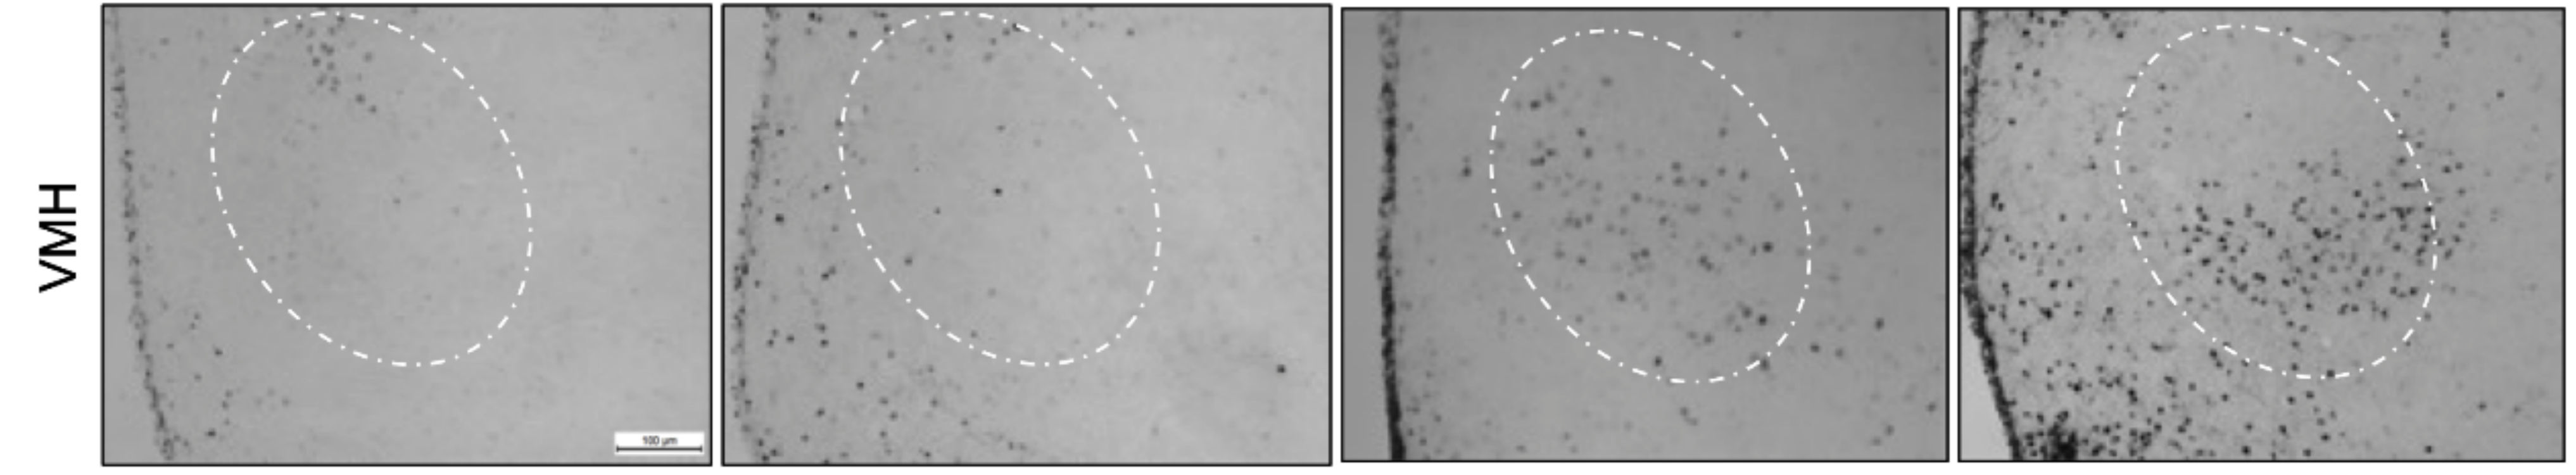

3.3. The Prolonged CB2 Receptor Activation Increased Astrogliosis in the VMH of HFD-Fed Mice